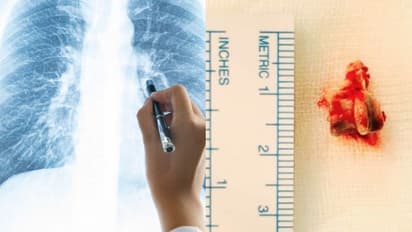

കൊച്ചി: ശ്വാസകോശത്തിൽ നിന്ന് കണ്ടെത്തിയത് കോഴിക്കറിയിലെ എല്ല്. മൂന്ന് വർഷമായി ശ്വാസകോശ സംബന്ധിയായ ബുദ്ധിമുട്ടുകൾ കൊണ്ട് വലഞ്ഞ പെരുമ്പാവൂർ സ്വദേശിയായ 62കാരന്റെ ശ്വാസകോശത്തിൽ നിന്നാണ് കറിയിൽ നിന്നുള്ള എല്ല് നീക്കം ചെയ്തത്. വളരെ നീണ്ട് നിൽക്കുന്ന ചുമയും ശ്വാസതടസവും ഇടവിട്ടെത്തുന്ന പനിയുമായിരുന്നു 62കാരനെ വലച്ചിരുന്നത്. രണ്ട് ആഴ്ച മുൻപാണ് 62കാരൻ വിദഗ്ധ ചികിത്സ തേടി അമൃത ആശുപത്രിയിൽ എത്തിയത്. എക്സ് റേ പരിശോധനയിലും സി ടി സ്കാനിലും ശ്വാസകോശത്തിൽ അന്യവസ്തുവുള്ളതായി കണ്ടെത്തുകയായിരുന്നു. ശ്വാസകോശത്തിന്റെ വലത്തേ നാളിയുടെ താഴ്ഭാഗത്താണ് എല്ല് കുടുങ്ങിയത്.

അന്യവസ്തുവിന് പുറമേയ്ക്ക് ദശ വന്ന നിലയിലായിരുന്നു എല്ലിന്റെ ഭാഗമുണ്ടായിരുന്നത്. ഫ്ലെക്സിബിൾ ബ്രോങ്കോസ്പി എന്ന രീതിയിലൂടെയാണ് എല്ലിൻ കഷ്ണം കണ്ടെത്തിയത്. ദ്രവിച്ച് രണ്ട് ഭാഗങ്ങളായി മുറിഞ്ഞ അവസ്ഥയിലാണ് എല്ല് പുറത്തെടുത്തത്. രണ്ട് സെന്റിമീറ്ററോളം നീളമുള്ള എല്ലിൻ കഷ്ണമാണ് പുറത്തെടുത്തത്. എക്സ് റേ പരിശോധനയിൽ ശ്വാസകോശത്തിൽ അന്യ വസ്തു കണ്ടെത്തിയതിന് പിന്നാലെയാണ് ഇയാൾ വിദഗ്ധ ചികിത്സ തേടി കൊച്ചിയിലെത്തിയത്.

കൊച്ചി അമൃത ആശൂപത്രിയിലെ പൾമണോളജി വിഭാഗത്തിൽ ഇന്റർവെൻഷണൽ പൾമണോളജി വിഭാഗം മേധാവി ഡോ.ടിങ്കു ജോസഫിന്റെ നേതൃത്വത്തിലുള്ള ഡോക്ടർമാരുടെ സംഘമാണ് ശസ്ത്രക്രിയ കൂടാതെ ശ്വാസകോശത്തിൽ നിന്ന് കോഴിക്കറിയിലെ എല്ല് പുറത്തെടുത്തത്. ഡോ. ശ്രീരാജ് നായർ, ഡോ അമൽ രാജ് എന്നിവരാണ് ഡോ.ടിങ്കു ജോസഫിനൊപ്പം പ്രൊസീജ്യറിൽ പങ്കെടുത്തത്.